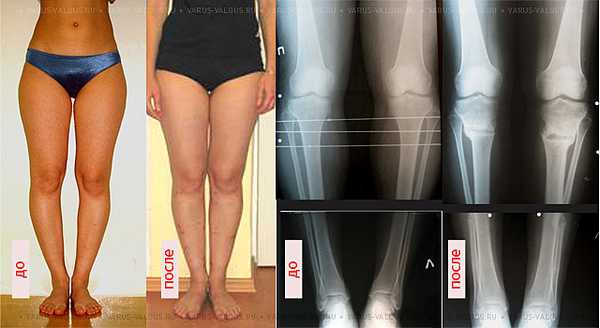

Внешний вид и рентгенограммы девушки 19 лет с эстетически неблагоприятным распределением мягких тканей на голени до и после угловой коррекции и медиализации

По желанию пациентов угловая коррекция дополняется медиализацией почти в 60% случаев и значительно улучшает эстетический эффект.